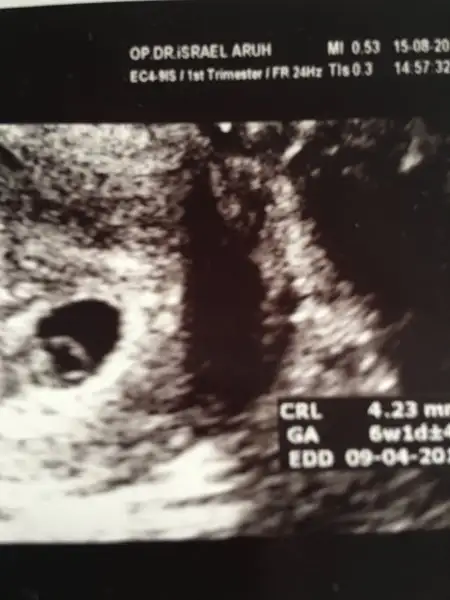

Bu arada ben de gördüm miniğimi kalp atışını da duydum. Çok güzel bir duygu. Sağ salim devam eder umarım. Ultrason ölçümüne göre 6+1 sat a göre 6+5 doktorum sat esas almalıyız dedi. Allah isteyen herkese kısmet etsin. Hepimizin gebelikleri sağ salim geçsin inşallah.

Kizlar ultrason fotoraflarimizi ekleyelim ben yarin gidicem yarin eklerim buraya

Bugün bende aynısını yaşıdım yedi haftalık olmam gerekirken 6+5 görünüyor korkacak bişey yok dedi doktor tüplerden geç ilerlemiştir ondan öyle gözükür dedi

Teşekkür ederim canım sat göre yedi haftalık ama ultrasyonda 6+5 gözüküyor